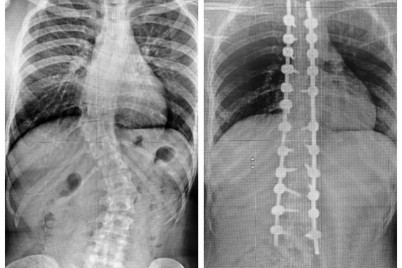

أنهى فريق طبي بمستشفى الدكتور سليمان الحبيب بالقصيم، معاناة شابة تبلغ من العمر 18 سنة، كانت تعاني من انحراف...